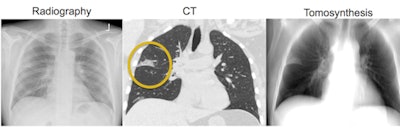

Conventional chest radiograph (left) and simulated tomosynthesis image (right) for the same patient. Middle image shows a coronal CT slice that demonstrates early pneumonia. Note how this abnormality is clearly demonstrated in the tomosynthesis image but is more subtle in the radiograph. Image courtesy of Dr. Gregory Kicska, PhD.The area under the curve (AUC) for the observers grading the nodules was 0.85 for tomosynthesis and 0.80 for conventional radiography, the researchers found. While the difference was not statistically significant, with a p-value of 0.28, the finding hints at a performance advantage for tomo that could be borne out in a real-world environment with actual DR tomo systems, according to Kicska.